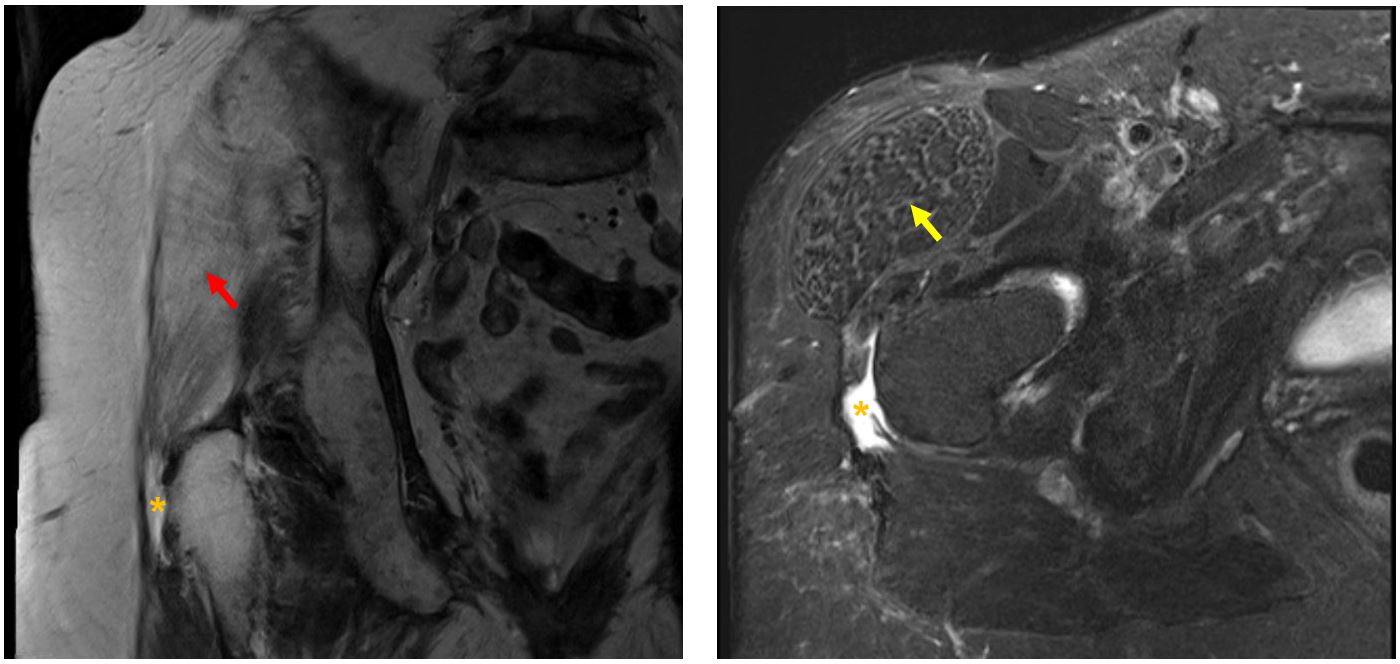

Die Tendinopathie der Hüftabduktoren wird anhand der klinischen Untersuchung und der Röntgenbilder diagnostiziert. In der klinischen Untersuchung fallen oft ein Hinken und Schmerzen über dem grossen Rollhöcker (Trochanter major) auf, die sich im Röntgenbild als Verkalkungen oder Enthesiophyten (Knochensporne) erweisen. Eine MRI-Untersuchung ist für die Diagnose nicht entscheidend, wird aber durchgeführt, wenn trotz gezielter Therapie die Beschwerden andauern, der Kraftgrad deutlich vermindert ist oder bei extremem Schmerz. Differentialdiagnostisch kommt eine Nervenwurzelkompression in Frage, die eine Wirbelsäulenabklärung erfordert. Auch Spannung im Schenkelbindenspanner (ein äusserer Hüftmuskel) und ein iliotibiales Bandsyndrom (ITBS) können Schmerzen um den Trochanter auslösen. Das ITBS betrifft häufig Langstreckenläuferinnen und Radfahrer, die durch Überlastung des Tractus iliotibialis Schmerzen im äusseren Kniebereich empfinden.

Bild: Universitätsklinik Balgrist